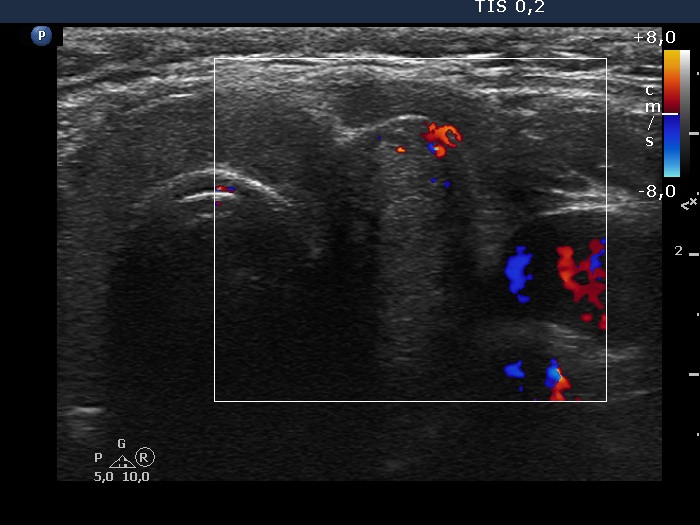

Left lobe, transverse scan, color Doppler mode. The vascularization is not specific.